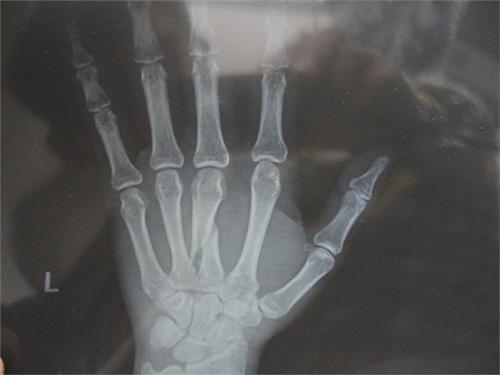

骨折有開放性骨折和閉合性骨折。

開放性骨折:骨折附近的皮膚和粘膜破裂,骨折處與外界相通恥骨骨折引起的膀胱或尿道破裂,尾骨骨折引起的直腸破裂,均為開放性骨折。因與外界相通,此類骨折處受到污染;

閉合性骨折:骨折處皮膚或粘膜完整,不與外界相通。此類骨折沒有污染。